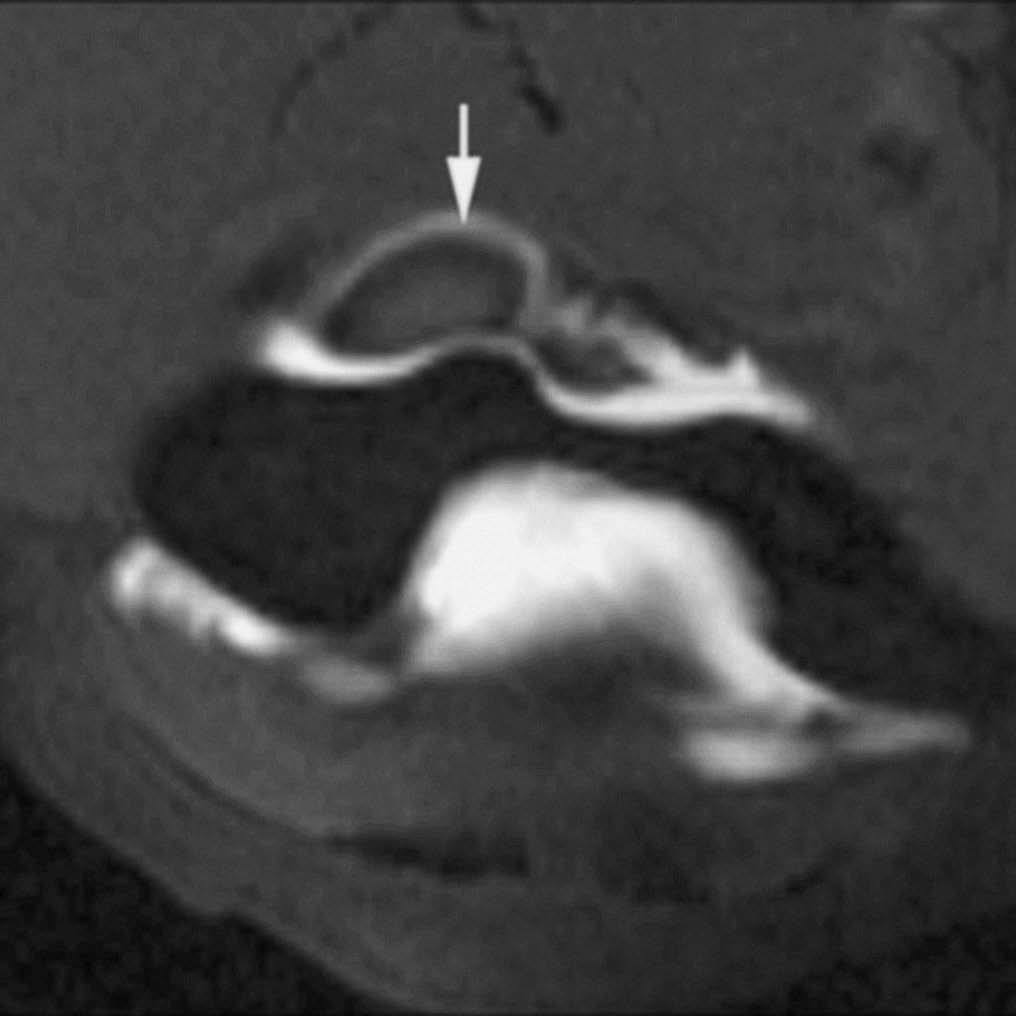

Fig. 10.--Síndrome de choque antero-lateral. Corte axial de RMA potenciado en T1 que muestra un tejido fibroso irregular ocupando el receso capsular antero-lateral (flechas).